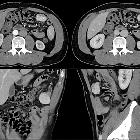

Solitärer

fibröser Tumor des Omentum in der Computertomografie oben axial arteriell und portalvenös, unten koronar und sagittal portalvenös. Beachte auch den Gefäßstiel.